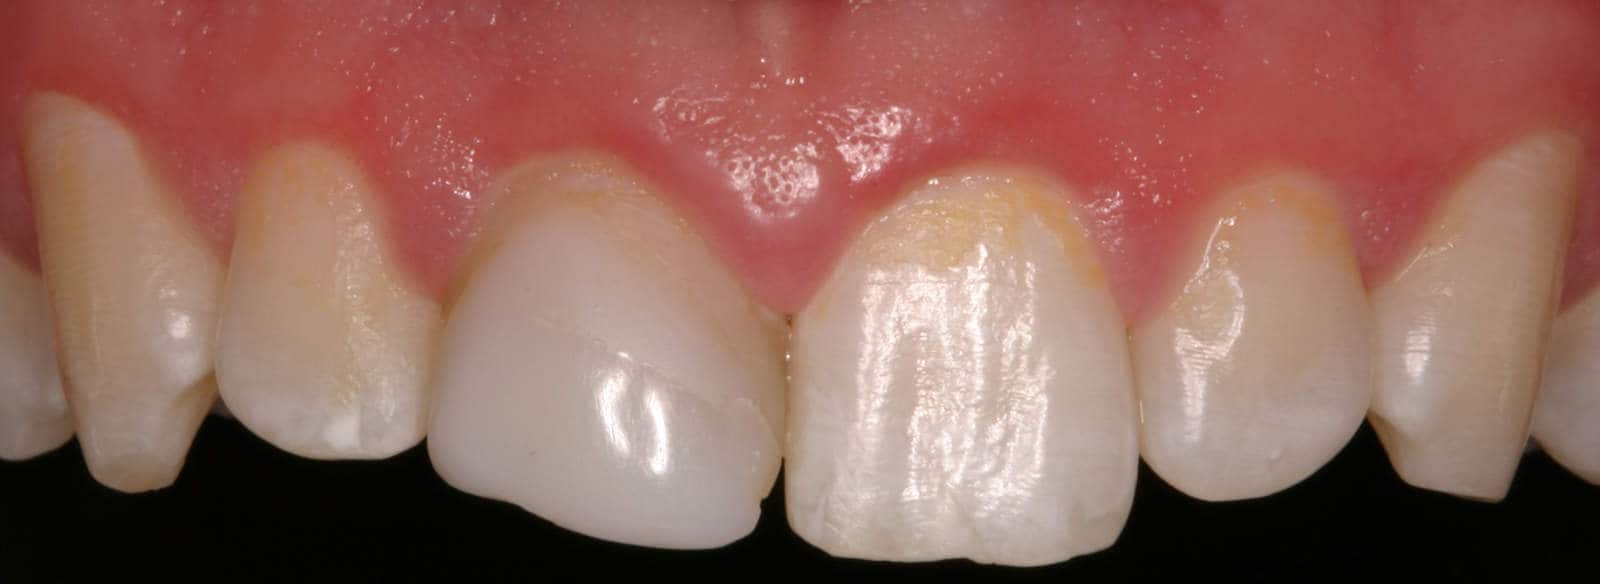

After: Followed by delivery of a custom ceramic post/core foundation, and a bonded all-ceramic full coverage single restoration (crown).